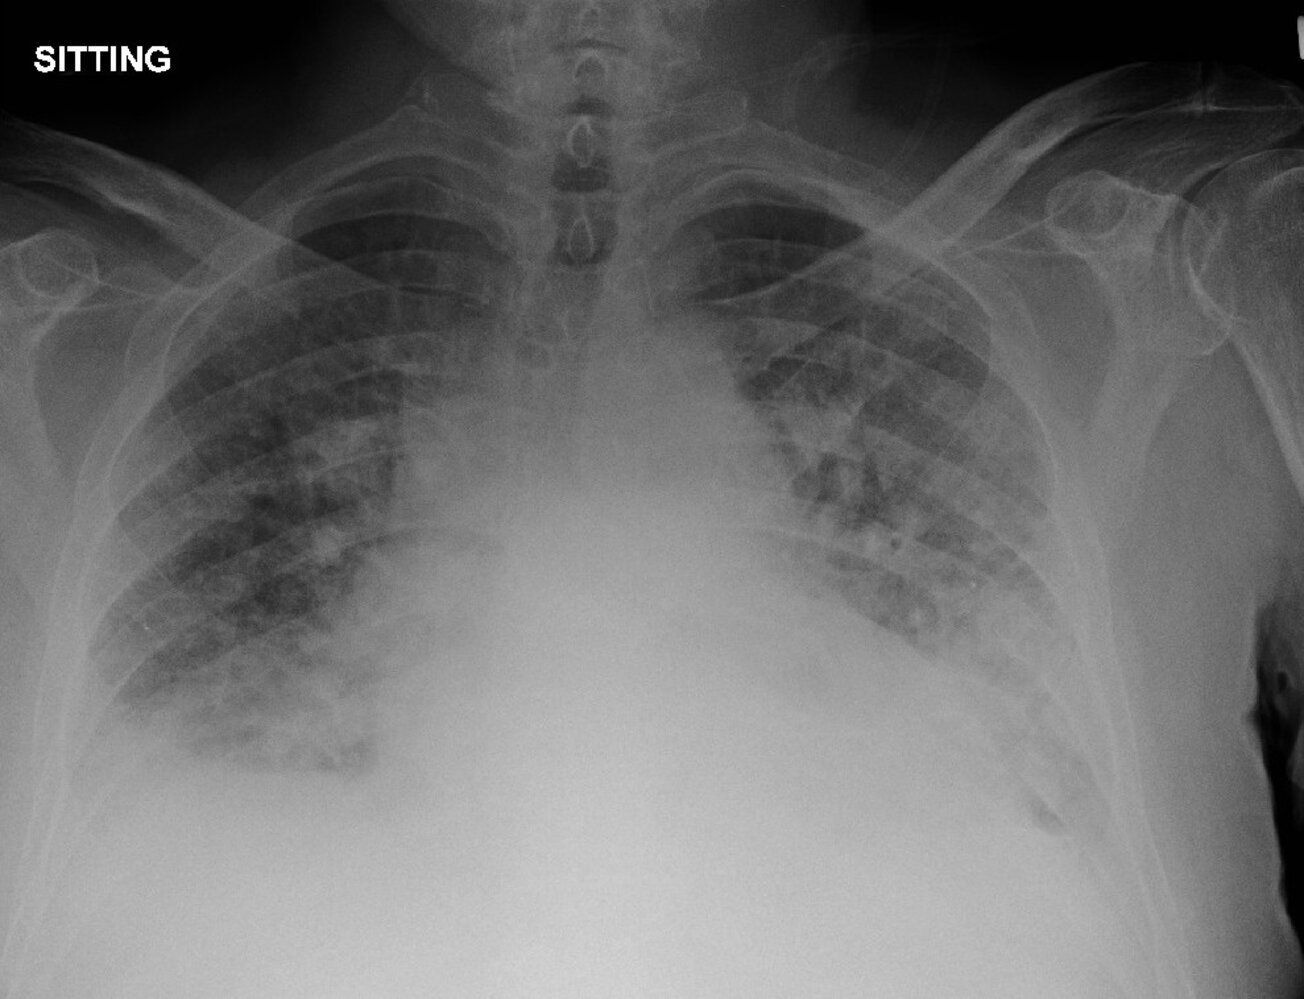

Chest x-ray [7][20]

-

Chest x-ray findings in cardiogenic pulmonary edema

- Enlarged heart shadow due to cardiomegaly and/or pericardial effusion [21]

- Kerley B lines (also known as septal lines)

- Prominent pulmonary vessels and perihilar alveolar edema (the hilar shadow has a butterfly or “bat wing” appearance)

- Basilar interstitialedema

- Bilateral pleural effusions [22]

- Cephalization: increased prominence of pulmonary vessels in the upper lobes of the lungs due to venous congestion [23]

- Peribronchial cuffing

ABCDE: Alveolar edema (bat wings), Kerley B lines (interstitial edema), Cardiomegaly, Dilated prominent pulmonary vessels, and Effusions